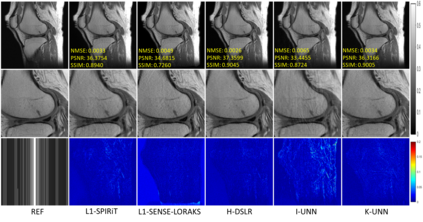

Recently, untrained neural networks (UNNs) have shown satisfactory performances for MR image reconstruction on random sampling trajectories without using additional full-sampled training data. However, the existing UNN-based approach does not fully use the MR image physical priors, resulting in poor performance in some common scenarios (e.g., partial Fourier, regular sampling, etc.) and the lack of theoretical guarantees for reconstruction accuracy. To bridge this gap, we propose a safeguarded k-space interpolation method for MRI using a specially designed UNN with a tripled architecture driven by three physical priors of the MR images (or k-space data), including sparsity, coil sensitivity smoothness, and phase smoothness. We also prove that the proposed method guarantees tight bounds for interpolated k-space data accuracy. Finally, ablation experiments show that the proposed method can more accurately characterize the physical priors of MR images than existing traditional methods. Additionally, under a series of commonly used sampling trajectories, experiments also show that the proposed method consistently outperforms traditional parallel imaging methods and existing UNNs, and even outperforms the state-of-the-art supervised-trained k-space deep learning methods in some cases.